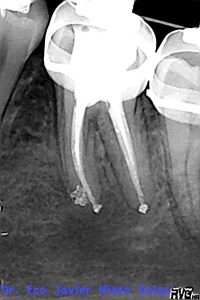

Presentaba una lesión periapical crónica, su diagnóstico es una necrosis pulpar con periodontitis apical crónica.

Le realizamos el tratamieto endodóntico del sistema de conductos en dos sesiones, soy un fiel defensor del medicameento intraconductos por varios motivos que quizás no sea el momento de comentar.

Usamos la técnica de ola continua de calor descrita por Buchanan y el backfilling se hizo con gutapercha inyectada.